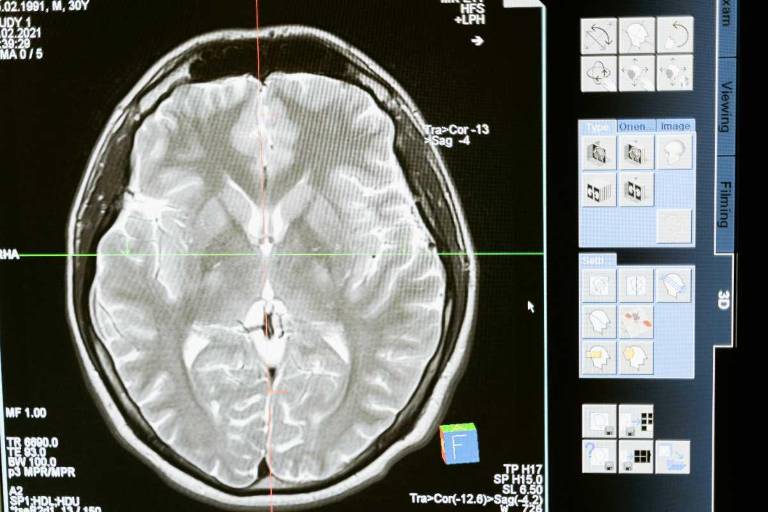

Según expertos de National Geographic, la presencia de vitamina B en el cerebro es de vital importancia, ya que desencadena una serie de beneficios cruciales para el organismo. Esta vitamina contribuye significativamente a la producción de energía y a la síntesis de componentes fundamentales como el ADN y el ARN.